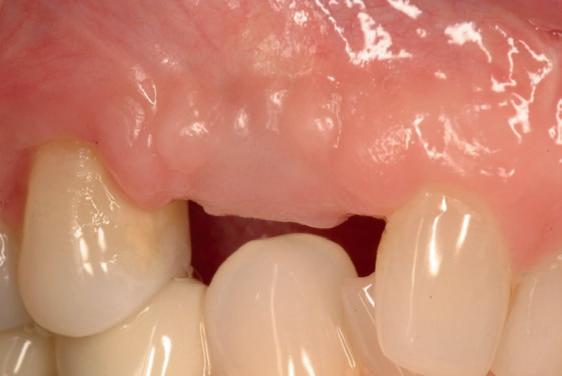

Twee weken later zie ik de patiënt terug voor controle van de eerste wondgenezing. De noodprothese mag de eerste twee weken niet gedragen worden en wordt tijdens de controle zorgvuldig aangepast aan de nieuwe situatie. Hiervoor wordt de prothese gedeeltelijk uitgefreesd en voorzien van een Soft Reliner materiaal. Te veel druk op de beide kaken moet ten alle tijden voorkomen worden en heeft effect op de ingroei van de botopbouw. De genezingsperiode duurt tenminste zes maanden voordat verdergegaan kan worden met de tweede fase: de abutment chirurgie. Hierbij wordt extra aandacht besteed aan het herstel van de gekeratiniseerde gingiva rondom de abutments. Dit komt ten goede aan de uitvoering van de mondhygiëne en dus de stabiliteit van de peri-implantaire mucosa. Deze ogenschijnlijk eenvoudige behandeling is essentieel voor de prognose van de implantaten op de lange termijn. Te weinig gekeratiniseerde mucosa maakt zelfzorg (borstelen/interdentaal reinigen) vaker pijnlijk of lastig, waardoor plaque en mucositis makkelijker kunnen ontstaan en blijven over de lange termijn. Dat kan bij patiënten die vatbaar zijn voor peri-implantitis zich vertalen naar crestaal botverlies rondom implantaten. Gek genoeg wordt de essentie van het herstellen van de gekeratiniseerde gingiva rondom implantaten regelmatig genegeerd.

Herstel van gekeratiniseerde mucosa en weke delenmanagement

De breedte en kwaliteit van de peri-implantaire mucosa beïnvloeden niet alleen esthetiek, maar met name de uitvoerbaarheid van zelfzorg en de stabiliteit van de mucosale barrière. Consensus reports en meta-analyses laten zien dat een beperkte of afwezige col van gekeratiniseerde peri-implantaire mucosa (vaak gedefinieerd als <2 mm) geassocieerd kan zijn met (1) meer plaque-accumulatie, (2) meer wekedelen-inflammatie, (3) meer mucosale recessie, (4) meer marginaal botverlies en (5) een hogere prevalentie van peri-implantitis.4-6 In de dagelijkse praktijk is dit vooral relevant bij full-arch restauraties waarbij de connectie prothese-abutments en de overgang prothese-mucosa moeilijker te reinigen zijn. Bij onvoldoende gekeratiniseerde mucosa of een ondiepe omslagplooi wordt poetsen vaak pijnlijk, waardoor plaquecontrole onvoldoende is en peri-mucositis gemakkelijk ontstaat. Dit verdedigt de indicatie voor een wekedelen augmentatie als chirurgisch onderdeel van de implantologische behandeling. Streefwaarde van ongeveer ≥2 mm gekeratiniseerde mucosa rondom implantaten wordt in de literatuur vaak gehanteerd.4, 5 Technisch kan dit in de tweede fase (abutmentchirurgie) voorafgaand aan de prothetiek worden uitgevoerd met een apicaal gepositioneerde flap, al dan niet gecombineerd met een gesteelde dan wel een vrij bindweefseltransplantaat (free gingival graft, FGG). FGG geldt als ‘standard of care’ voor voorspelbare toename van gekeratiniseerde mucosa. Xenogene collageenmatrixen kunnen in geselecteerde gevallen een alternatief zijn, bijvoorbeeld om donor site morbiditeit te beperken.4 Waar dikte en contour belangrijk zijn (recessies/esthetiek) wordt vaker een bindweefseltransplantaat overwogen.

In de prothetische fase (zie foto’s) is in de bovenkaak gebruikgemaakt van verschroefde zirconia bruggen, die enkel buccaal zijn opgebakken. Deze bruggen zijn verlijmd op individuele, geanguleerde titanium abutments. In de onderkaak is een verschroefde kunststofbrug op een titaniumbasis (wrap-around) gemaakt. Voor deze combinatie is gekozen vanwege een minder hinderlijk tikkend geluid bij functie en kleinere kans op breuk van de keramiek. Een nadeel is verhoogde slijtage van de kunststof elementen, maar deze zijn in de jaren later eenvoudig te vervangen op de bestaande brug. Ondanks alle digitale mogelijkheden is de afdruk en registratiefase analoog uitgevoerd, omdat in ervaring van de behandelaren dit bij deze totale rehabilitaties op implantaten nog altijd de grootste precisie oplevert. Er is afgedrukt met impregum in individuele lepels en de pasvorm is gecontroleerd met rigide duralay bars. De relatie wordt vastgelegd zoals bij een volledige prothese met waswallen en pijlpuntregistratie. De opstelling in was wordt gepast en laatste correcties worden gemaakt in samenspraak met de patiënt, de restauratieve tandarts en de tandtechnicus. Na het vastzetten van de suprastructuren worden de schroefgaten afgesloten met composiet.